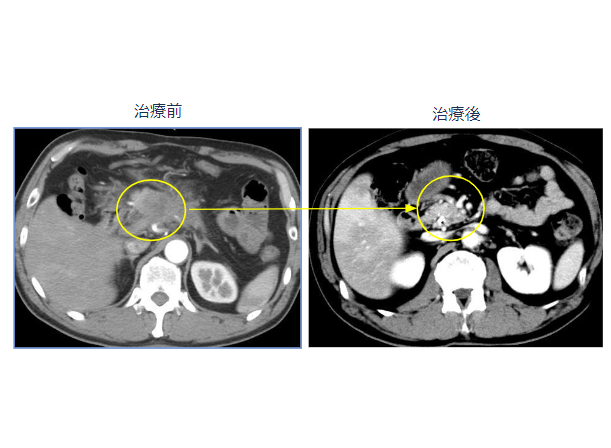

膵臓がんステージ4、腹膜播種が消失